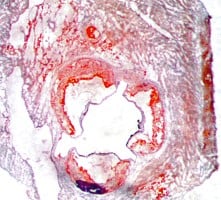

Atherosclerosis Aortic Root Histology Examples

Oil Red-O Staining (fat-soluble dye)